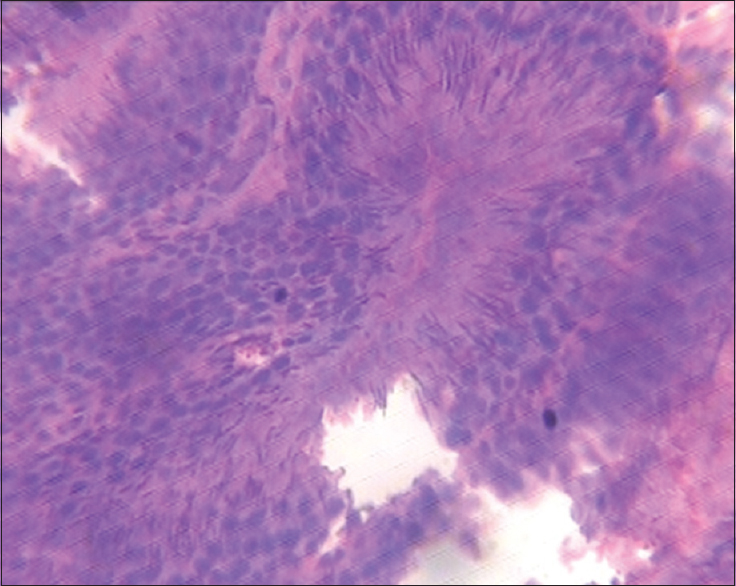

Figure 2: Testis (1000 mg/kg of monosodium glutamate)